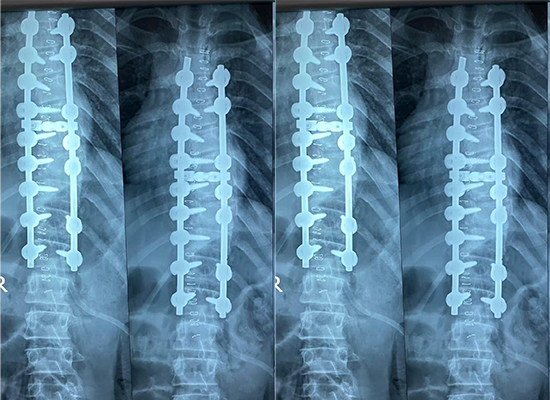

Для этой процедуры коррекции сколиоза в качестве основного решения для фиксации была выбрана Конструкции транспедикулярных винтов и стержней широко используются в хирургии деформаций позвоночника благодаря их способности обеспечивать прочную фиксацию позвонков и точный контроль выравнивания позвоночника. система транспедикулярных винтов диаметром 6,0 мм .

Система позволяет осуществлять трехмерную коррекцию, воздействуя на корональные, сагиттальные и аксиальные компоненты деформации позвоночника. Благодаря сегментарной фиксации на нескольких уровнях позвонков корректирующие силы могут быть распределены равномерно, поддерживая баланс позвоночника и снижая механическое напряжение в отдельных точках фиксации.

Во время процедуры использовались следующие имплантаты:

6.0 Полиаксиальный транспедикулярный винт

6.0 Кросслинк-I (SW3.5)

Эти компоненты работали вместе со стержнями для обеспечения стабильной конструкции заднего спондилодеза, подходящей для коррекции сколиоза у подростков.

Послеоперационная визуализация продемонстрировала улучшение выравнивания позвоночника по сравнению с дооперационным состоянием. Фиксирующая конструкция оказалась стабильной, поддерживая запланированную коррекцию. По словам хирургической бригады, у пациента наблюдалось удовлетворительное послеоперационное восстановление, без каких-либо немедленных осложнений, связанных с фиксацией.

Система транспедикулярных винтов диаметром 6,0 мм была выбрана для обеспечения стабильной сегментарной фиксации и поддержки трехмерной коррекции деформации позвоночника.

Полиаксиальные транспедикулярные винты позволяют упростить соединение стержней и регулировку их выравнивания, что полезно при сложных процедурах коррекции деформации позвоночника.

Поперечная связь может помочь повысить стабильность конструкции за счет улучшения устойчивости к вращательным силам, в зависимости от стратегии фиксации и уровня хирургического вмешательства.